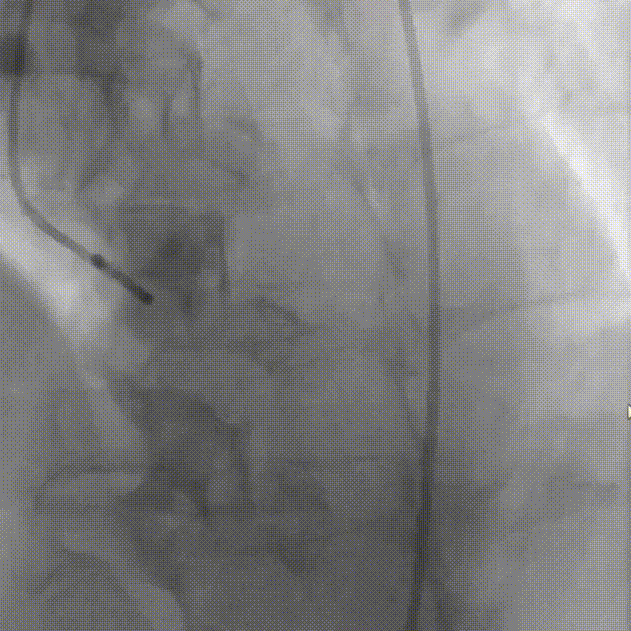

导丝跨瓣

主动脉根部造影